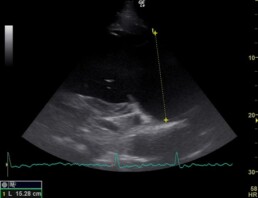

In der elektrokardiographischen und echokardiographischen Untersuchung zeigten sich die geringgradige Mitralklappeninsuffizienz (Schlussunfähigkeit der Herzklappe zwischen linkem Vorhof und linker Herzkammer), die geringgradige Trikuspidalkappeninsuffizienz (Herzklappe zwischen rechtem Vorhof und rechter Herzkammer), die geringgradige Aortenklappeninsuffizienz (Herzklappe zwischen linker Herzkammer und Aorta, Abb. 2) und das Vorhofflimmern (Herzarrhythmie) als unverändert. Die Herzdimensionsveränderungen liegen weiterhin vor, sind jedoch unverändert bis geringgradig verbessert (Abb. 1, 3).

Abb. 3: deutliche Dimensionsveränderung des linken Vorhofes in der linken kaudalen langen Achse (Referenzwert für Warmblüter: 13,5 cm)